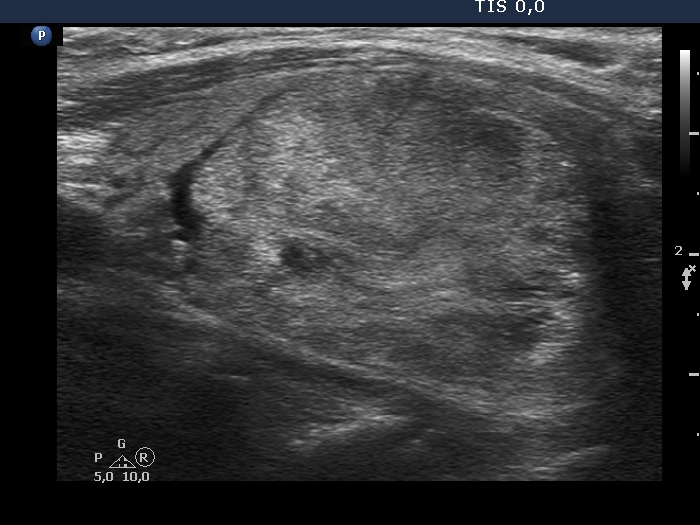

Ultrasonography. The thyroid was echonormal. There was an almost completely cyst in the right lobe. The left lobe was composed of a nodular area composed of multiple discrete lesions. The largest diameter of the nodular mass has increased from 15 mm to 37 mm in the last seven years. The size of the left lobe was 30x20x49 mm 7 years ago while the diameters were 39x23x58 mm at the present examination.